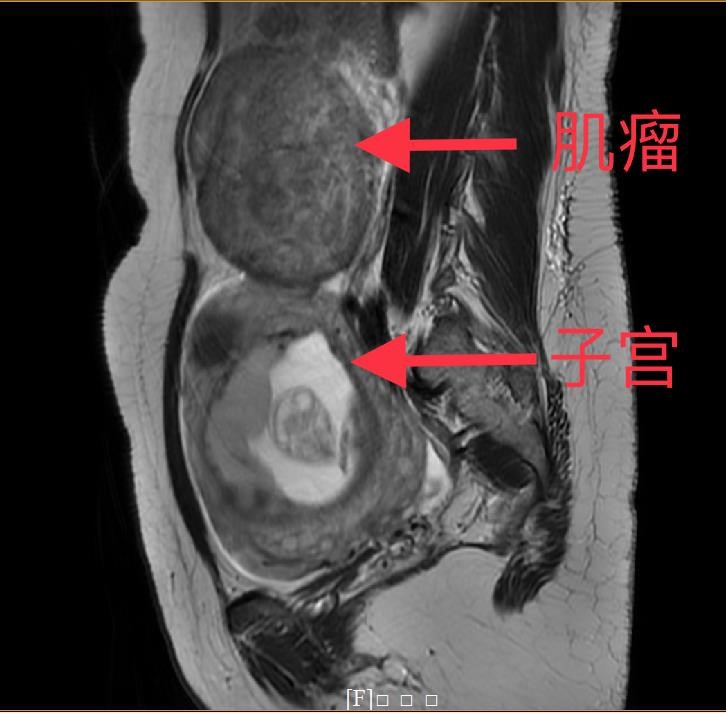

妊娠合并巨大子宫肌瘤

图片尺寸1600x1200